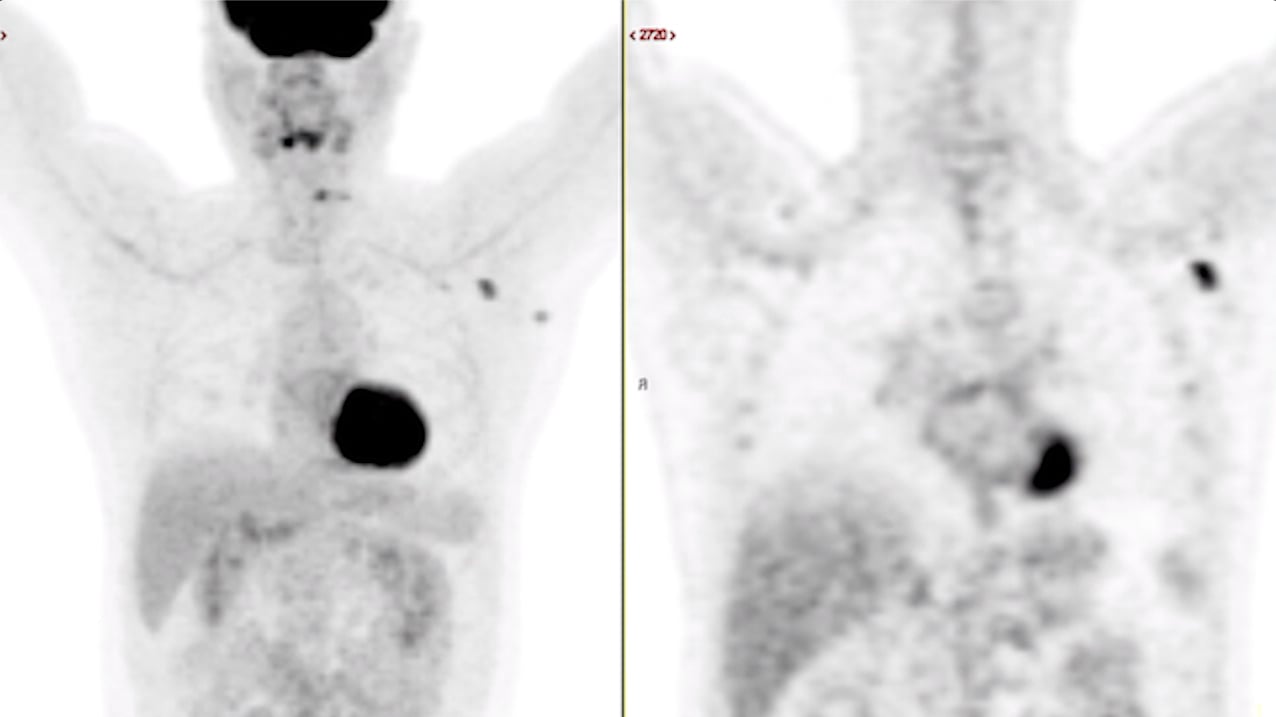

This photo gallery shows the variety of radiological presentations of COVID-19 (SARS-CoV-2) in medical imaging, including computed tomography (CT), radiograph X-rays, ultrasound, echocardiograms and magnetic resonance imaging (MRI). The radiology images show examples of typical COVID pneumonia in the lungs and the numerous complications the virus causes in the body in multiple organs, including the brain, kidneys, heart, abdomen and vascular system.

Ultrasound, especially hand-held ultrasound imaging devices, have become a primary imaging modality for novel coronavirus because of the ease to bag the device and sterilize it after use. CT and mobile X-ray systems are also used as front-line imaging systems for COVID-positive or suspected COVID patients.